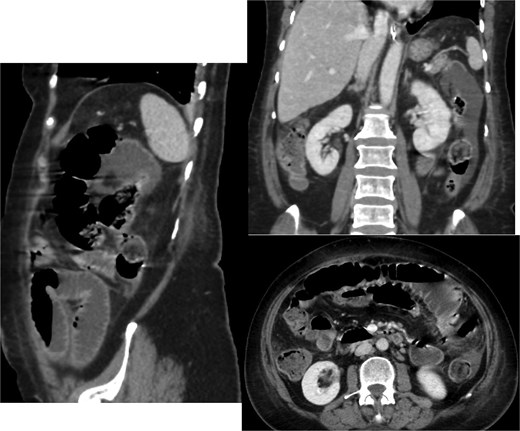

A CT scan of the abdomen revealed (Fig. 1):

A thickened gallbladder with a cholecystoduodenal fistula

A 22-mm gallstone impacted in the distal ileum causing high-grade small bowel obstruction

No signs of bowel ischemia, pneumoperitoneum, or intra-abdominal collections

No evidence of diverticulitis

Contrast-enhanced CT scan of the abdomen and pelvis showing the small bowel loops are dilated reaching up to 35 mm. There is a transition zone with 22 mm gallstone in the distal ileum with distally collapsed ileal segments and collapsed large bowel loops representing high-grade obstruction. The gallbladder appears irregular with thickened wall and significant surrounding fat stranding. There is a fistula between the gallbladder and the second part of the duodenum.

Based on these findings, the diagnosis of gallstone ileus secondary to a cholecystoenteric fistula was made.